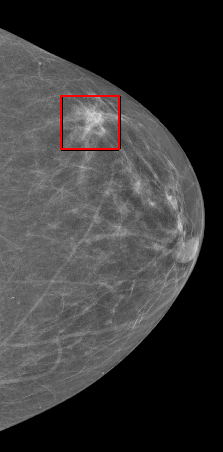

The Oregon-Massachusetts Mammography Database

OMAMA-DB

World's Largest Mammography Dataset

publicly available!

with labels!

we started with ~1 million images!

2000 x 2000 pixels

100 x 2000 x 2000 voxels

~8 MB

~500 MB

~8 TB